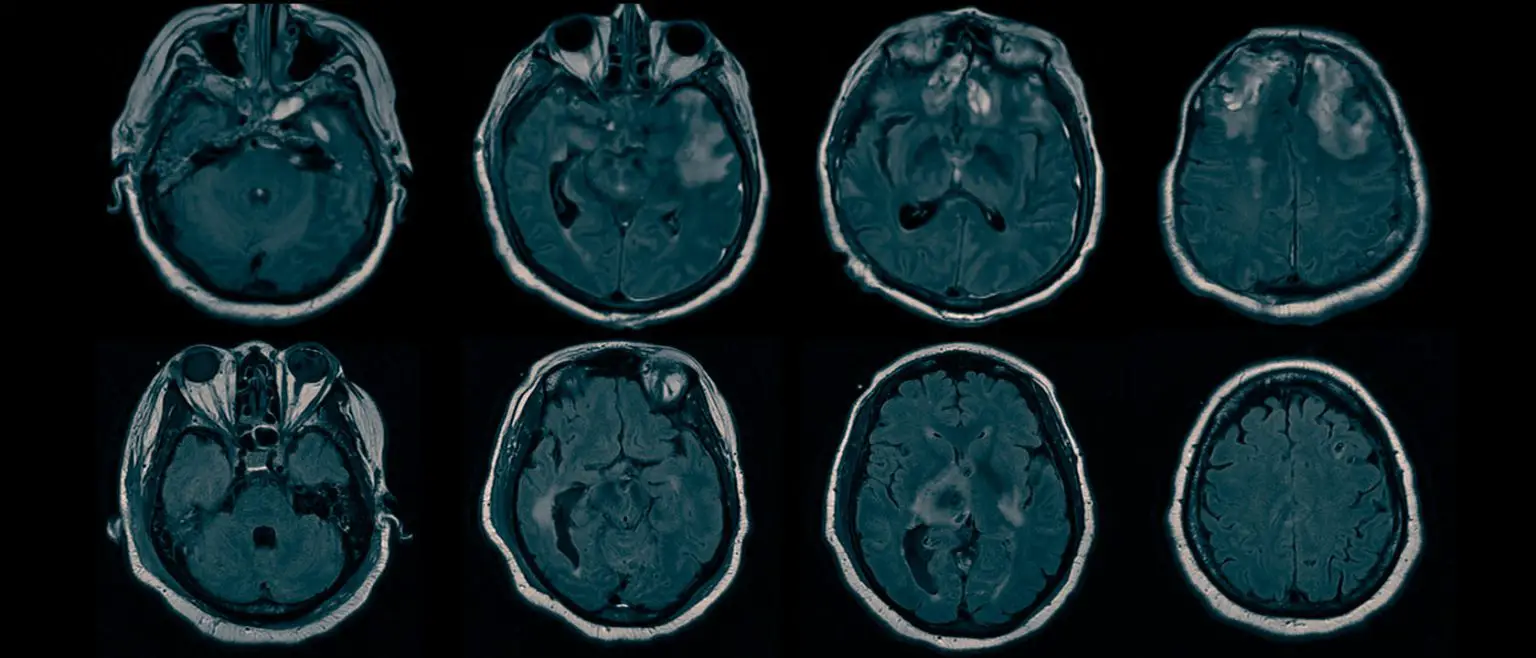

核磁共振成像扫描揭示了隐藏意识背后的脑损伤。资料来源:哥伦比亚大学欧文医学中心克拉森实验室

研究人员随后分析了所有患者的核磁共振成像结构扫描结果。

共同第一作者、克拉森实验室副研究员、信号处理、机器学习和生物统计学专家沈琦(音译)博士说:"利用我们开发的一种名为双聚类分析的技术,我们能够找出CMD患者共有的脑损伤模式,并与没有CMD的患者形成对比。"

研究人员发现,所有CMD患者都有与唤醒和指令理解相关的完整大脑结构,这支持了这样一种观点,即这些患者听到并理解了指令,但却无法执行。

克拉森说:"我们发现,所有CMD患者负责将理解的运动指令与运动输出相结合的大脑区域都存在缺陷,这使得CMD患者无法根据口头指令采取行动。"